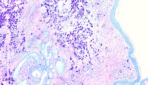

Giemsa-stain_Dog-Skin-Tumor